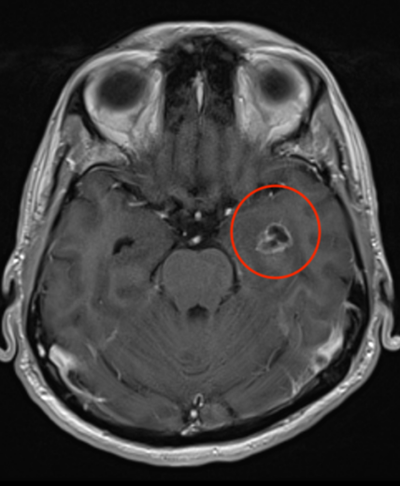

Sadayan nhận được tin tức khủng khiếp: Anh có một khối u hiếm ở thùy thái dương của não, với đường kính 2 - 3cm.

Chính khối u này đã tác động đến khu vực của não “phụ trách” các cảm xúc giận dữ, thịnh nộ và phản ứng căng thẳng cấp tính. Cũng chính nó đã khiến anh liên tục cáu kỉnh không có lý do, không thể kiểm soát.